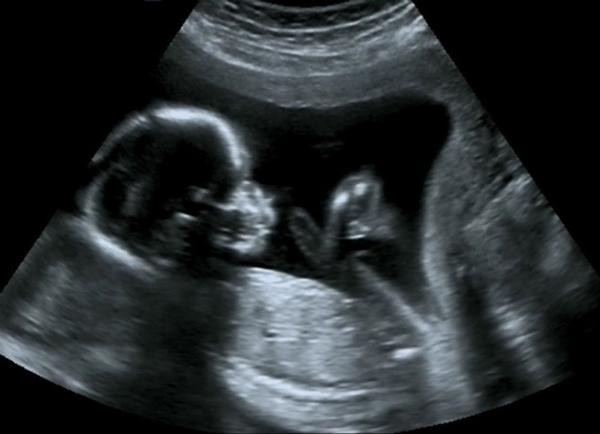

Những bệnh của con không thể phát hiện từ trong bụng mẹ

(Ngày Nay) - Siêu âm thai đóng vai trò quan trọng trong việc đảm bảo phát hiện kịp thời các vấn đề ở thai nhi, nhưng có một số bệnh ở thai nhi mà siêu âm cũng "bó tay", không thể phát hiện.

Ảnh minh họa